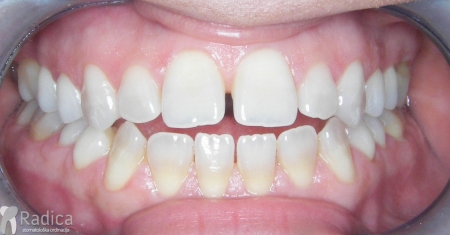

Slučaj 3: ispravljanje kompresije Invisalign full terapijom